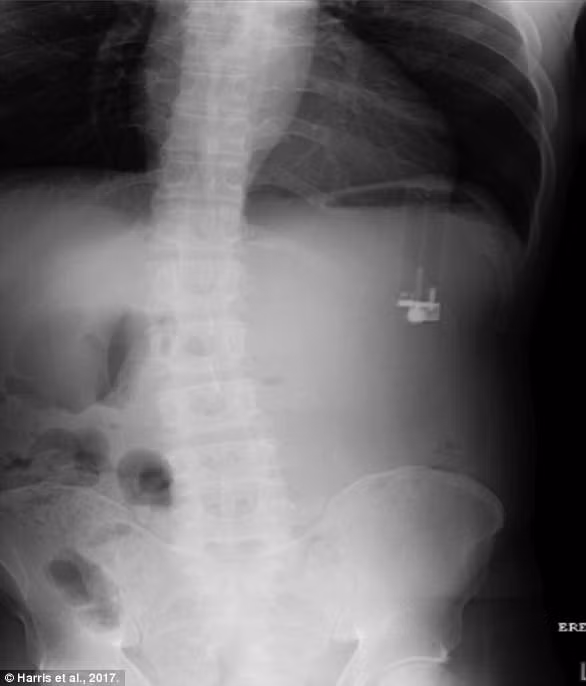

| Hình ảnh siêu âm cho thấy hơn 600 chiếc đinh trong bụng ông Dhali. Ảnh: SWNS. |

Các bác sĩ đã sốc khi ảnh chụp siêu âm cho thấy ông Dhali đã nuốt tổng cộng hơn 639 chiếc đinh sắt trong bụng. Loại đinh mà người đàn ông này nuốt là đinh sắt 5 phân, tổng cộng nặng tới 1,3kg.